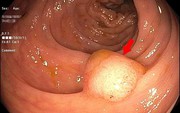

• Ngày càng nhiều chị em còn trẻ đã mắc ung thư cổ tử cung, bác sĩ khuyên: 4 món này ngon đấy nhưng ăn ít lại!

Ngày càng nhiều chị em còn trẻ đã mắc ung thư cổ tử cung, bác sĩ khuyên: 4 món này ngon đấy nhưng ăn ít lại!